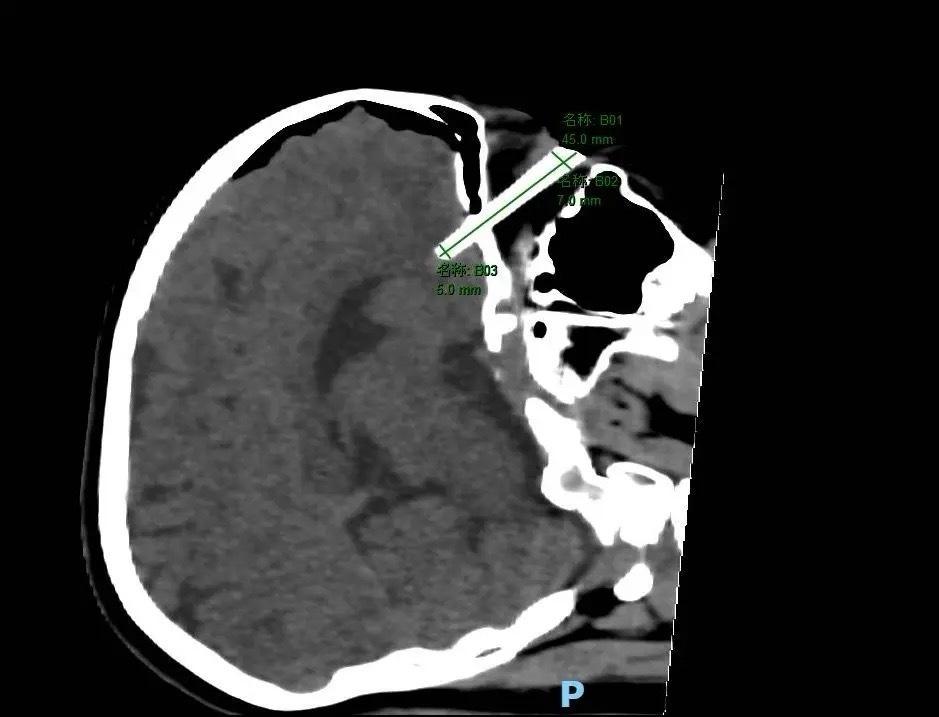

筷子直插入脑CT图

头部CT检查结果显示,筷子已穿透眼眶,进入脑内,导致小英右侧脑部出现内出血,情况极其危险。筷子紧挨着右眼球穿过,一旦拔除,极有可能引发颅内大量出血,需进行开颅手术,可能造成严重的神经、精神功能障碍,甚至导致右眼失明,以及脑脊液漏、颅内感染、癫痫发作等严重并发症。

在与家属充分沟通病情后,神经外科和眼科专家迅速联合为小英实施了右侧眶-颅内异物取出手术,成功取出了长约4.5厘米的筷子。